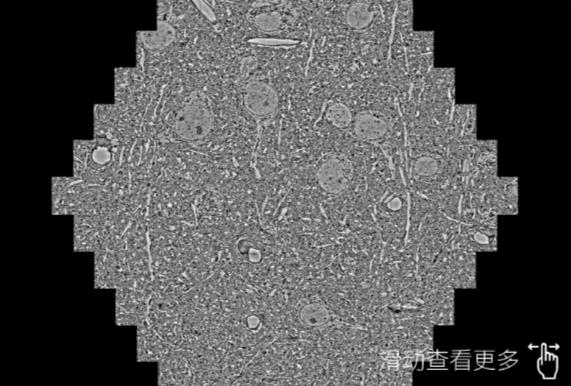

鼠脑切片。左图使用东营蔡司东营扫描电镜MultiSEM706对165μmx143pm面积区域成像,耗时仅需1.5秒。右图为鼠脑切片中30μm区域放大效果。样品由芝加哥大学B.Kasthuri提供。

使用蔡司高速东营扫描电镜MultiSEM对1mm²人脑皮层组织进行高分辨成像,并对其中的各种细胞结构进行三维重构分析。左图展示了2x3mm²组织平面中锥体神经元的三维重构效果。右图显示了局部体积神经元三维重构。图像由哈佛大学chtman实验室提供,渲染图由D. Berger 制作。